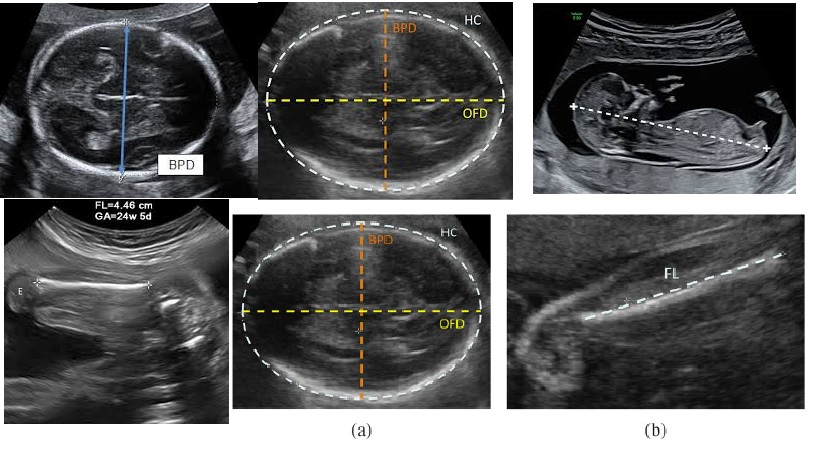

Fetal biometric measurements are important components for evaluation of fetal age on Ultrasound

Fetal biometry is a medical test used to assess the health and development of a fetus during pregnancy. This test uses ultrasound technology to measure the fetus's age, weight, and physical structure.

The technician will measure the fetus's age, weight, and physical structure